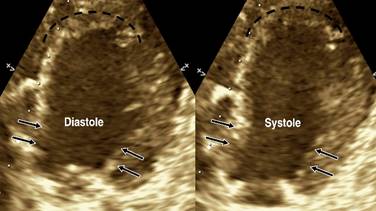

Table 1 shows the patients’ origin and demographics. Table 2 shows the basal patient’s characteristics, and Table 3 displays the diagnostic angiography and outcomes; Figure 1 displays the Killip-Kimbal class progress and Figure 2 the ejection fraction; Figure 3 shows an example of the echocardiographic in one of our patients, showing the characteristic apical ballooning on dotted lines and the typical basal contractility shown by the arrows.